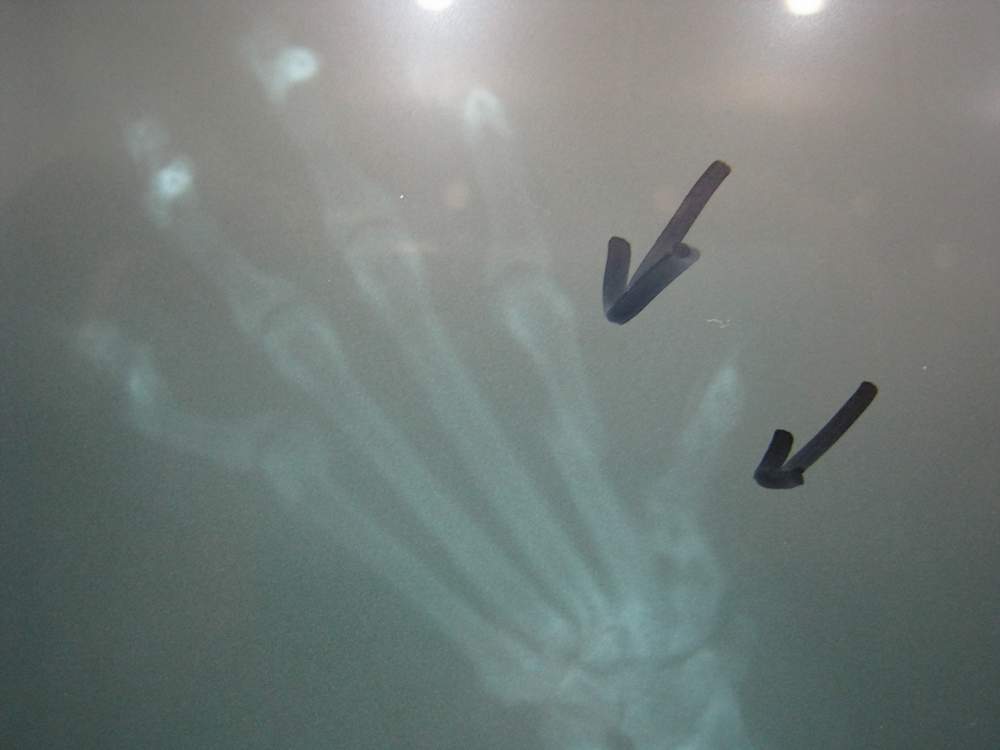

主題: 榮總保一總隊捕獸夾貓 申請者姓名: 楊凱蒂 花色: 申請日期: 2014-03-03 03:00:19 申請者部落格: 申請者臉書網址: https://www.facebook.com/katieyangdayounger1 所在縣市/合作醫院: 台北市/豐茂動物醫院 治療費用: 8400元 需求人數: 10人 已結案 (2014-03-24 18:16:25) 報名人員: Hide(已付款)、劉玉婷(已付款)、Rita Huang(已付款)、Caifu Hsiao(已付款)、Staru Chang(已付款)、natsui(已付款)、陳湘淇(已付款)、SASA(已付款)、小四 x2(已付款)、 候補人員: 動物病情說明: 12/20號榮總保一總隊的阿兵哥抓到這隻腳夾帶著捕獸夾的貓。 原本已經通知動保處來處置。志工聽聞,先提早一步盡快把貓攔截下來就醫。所幸貓咪被捕獸夾夾到的時日不久, 醫生判斷之下無需截肢。 但因為傷口腫大,外加手指兩處骨折。 先打長效性抗生素與清創。 貓咪尚未結紮, 麻醉了後也順帶結紮。 結紮費由志工自費。目前已送去合作醫院做第一時間的安置及治療。 動物近況說明: 賓賓休養期間傷口細菌感染, 導致手掌肉墊部份潰爛. 清創後剩餘2/3肉墊. 不影響行動, 但賓賓需要些許時間適應. 已接出醫院, 後續會轉到愛媽熟識的醫院, 安養一段時日在安排時間原地也放. 愛媽自費$3000並會自行負責後續醫療.